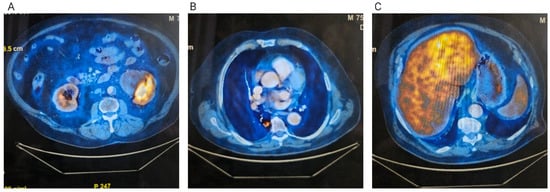

In June 2024, an 18F-fluorodeoxyglucose positron emission tomography–computed tomography (FDG PET-CT) scan confirmed a centrally cavitated right lower lobe lesion with a maximum standardized uptake value (SUVmax) of 3.91, a left lobe hepatic lesion with mildly increased metabolic activity (SUV 5.22 compared to a background SUV of 4.28 in the rest of the hepatic parenchyma), and a left renal mass with slightly increased uptake (Figure 1). Serum tumor markers obtained in April 2024 were within normal limits: carcinoembryonic antigen (CEA) 3.34 ng/mL, carbohydrate antigen 19-9 (CA 19-9) 6.21 U/mL, and alpha-fetoprotein (AFP) 1.87 ng/mL.

Figure 1. FDG PET-CT examination. (A) Left kidney tumor; (B) Right lung tumor; (C) Hepatic tumor.